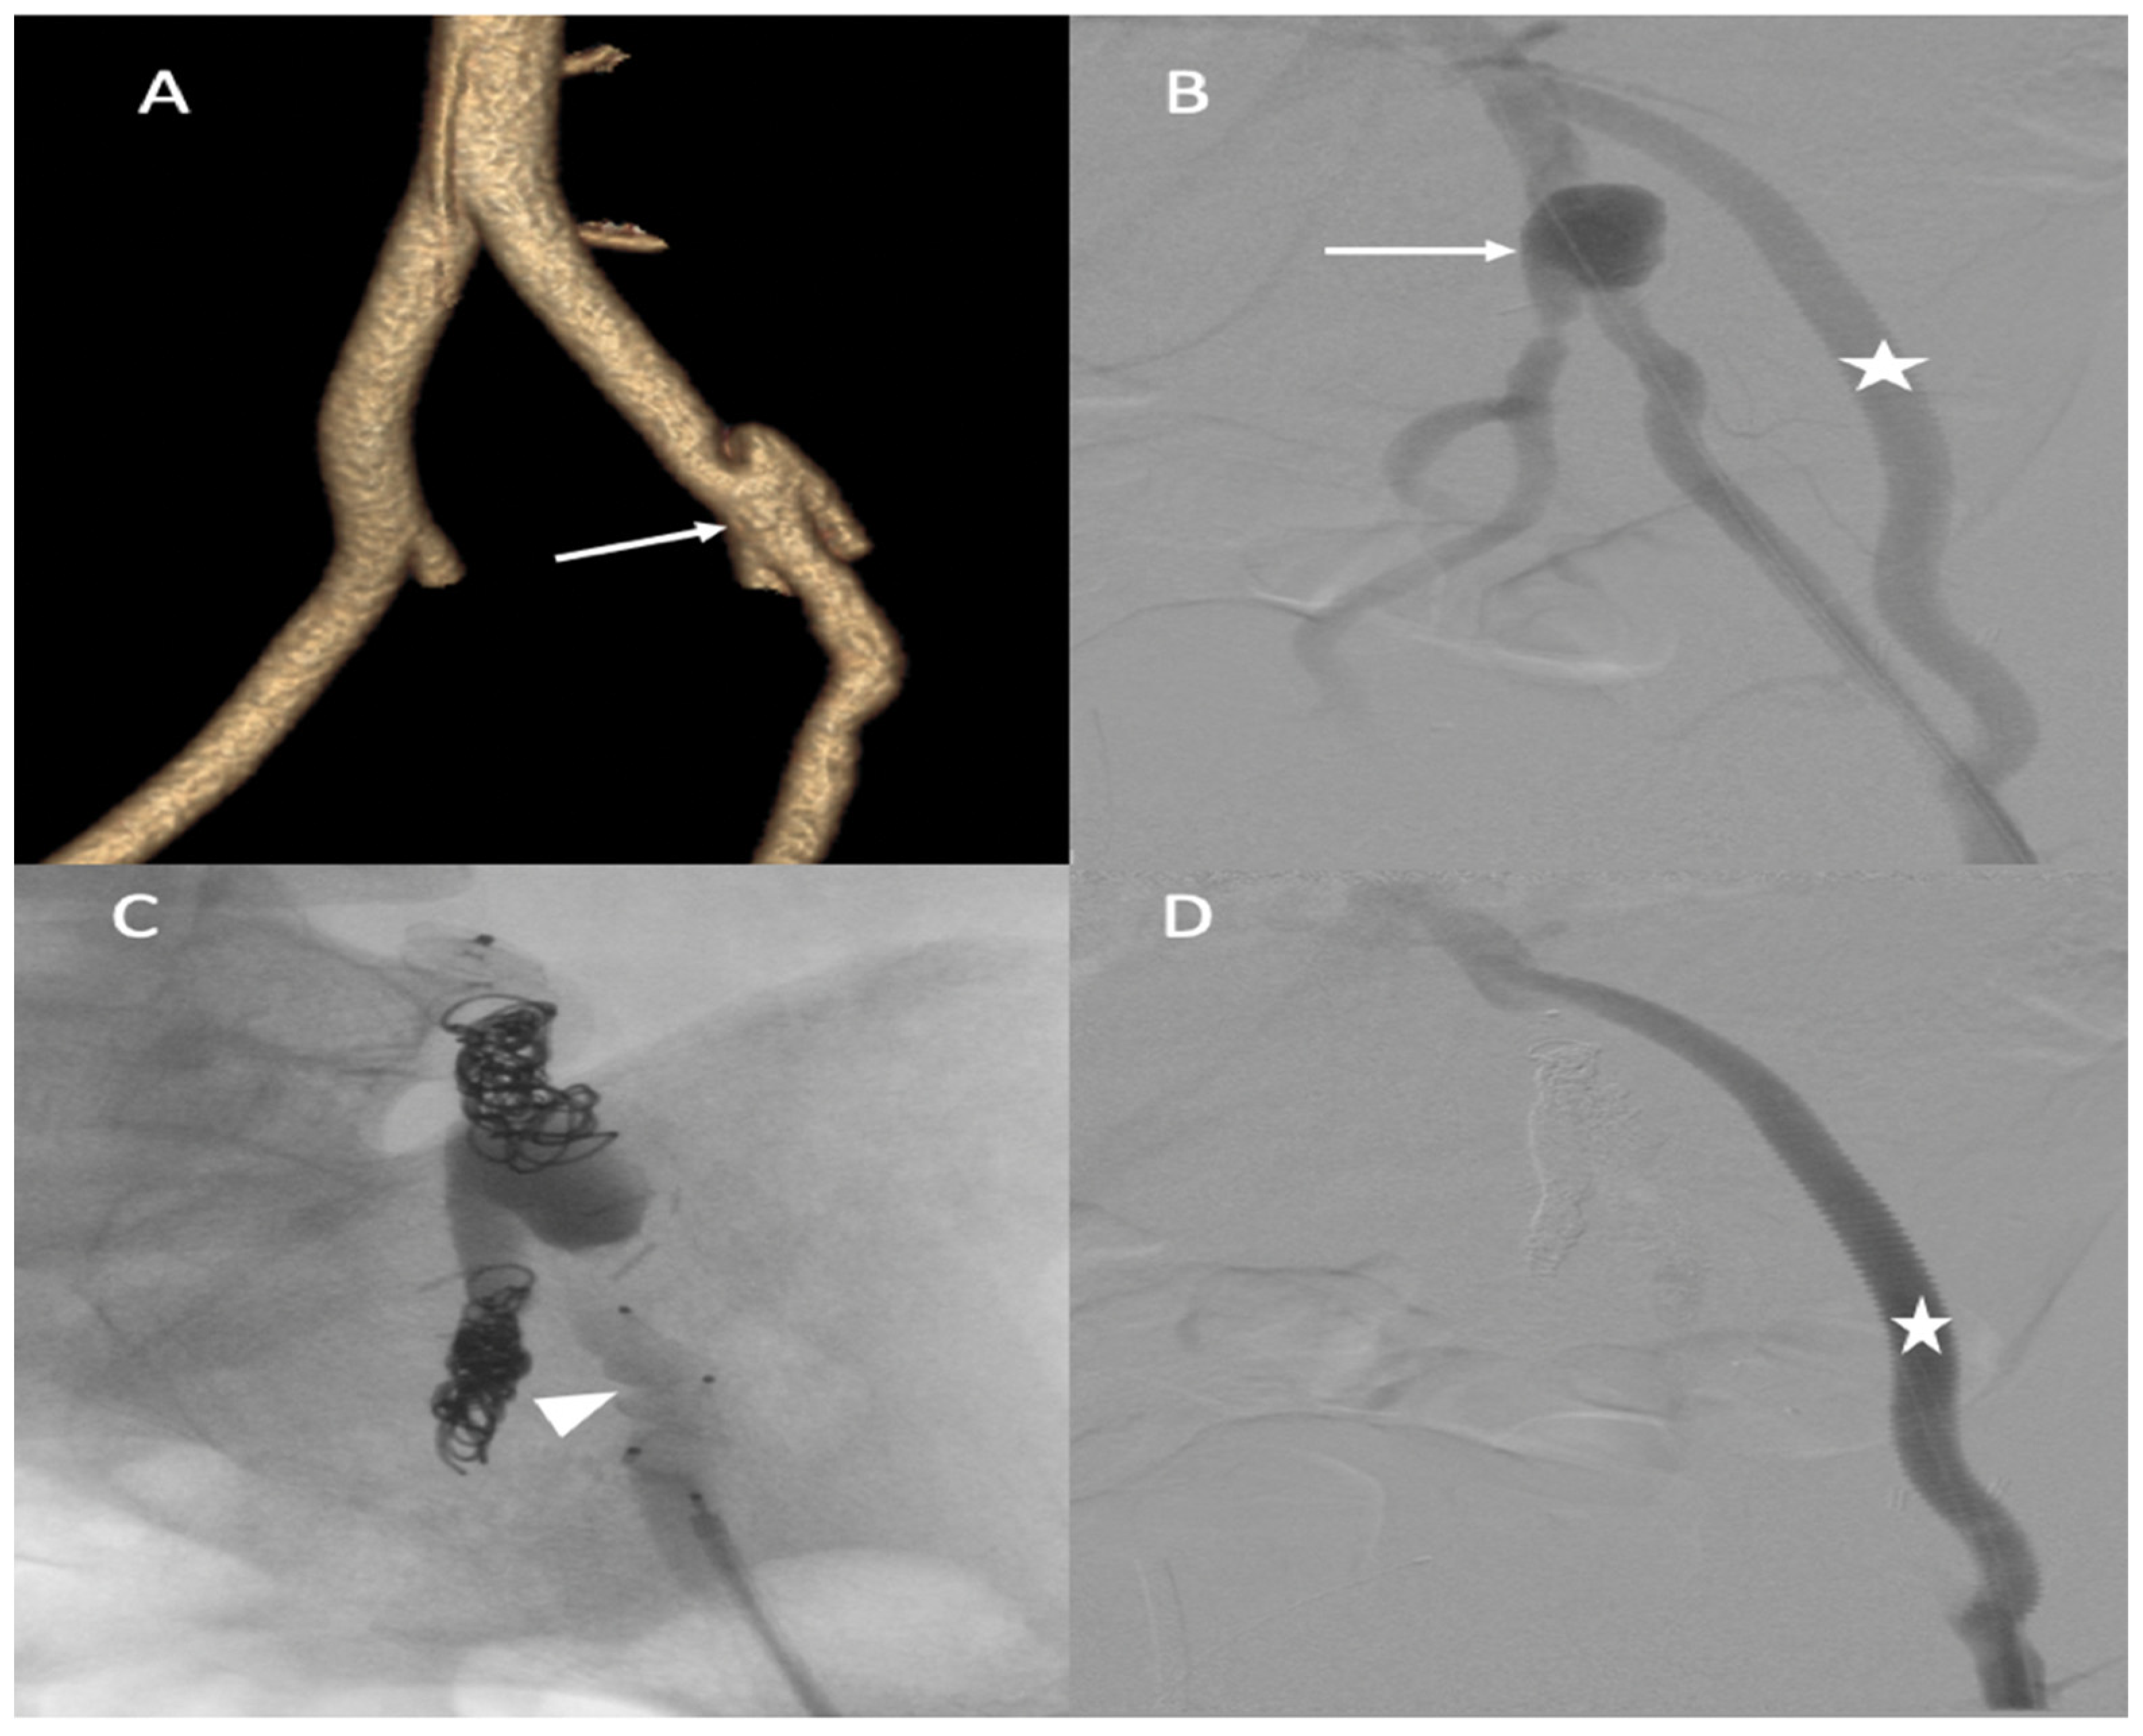

A 35-year-old male patient was admitted to the emergency department for acute abdominal pain. The CT scan showed a celiac trunk dissection extended to the hepatic and splenic arteries, a left renal artery dissection with an infarct and a right common iliac artery dissection with an aneurysmal formation (Figure 8A). The patient was monitored in the intensive care unit and treated with antihypertensive and analgesic anticoagulation therapy and strict rest. His clinical phenotype indicated vEDS according to the vascular medical team, and celiprolol was introduced. Four days later, he presented with recurrent abdominal pain associated with severe lumbar pain. A CT scan demonstrated a rapid diameter evolution of the left renal artery aneurysm and right common iliac artery dissection and a new dissection of the left common iliac and right renal arteries (Figure 8B). The pain regressed with blood pressure control and analgesics. A clinical and radiological follow-up was decided. One week later, due to the recurrence of lumbar and abdominal pain and aneurysmal evolution on two common iliac arteries, the patient was referred to a vascular surgeon and interventional radiologist. Under general anesthesia, we performed left hypogastric embolization by coils and endovascular exclusion of the left iliac artery with an aorto-iliac stent graft (Medtronic ETLW 16-10C124EE and ETEW 20-20C82EE). The contralateral iliac artery was embolized with second-generation 10 mm plugs (AMPLATZER-USA), and we performed a femoro-femoral bypass from the left to the right (Figure 8C).

Figure 8.

(A) Axial abdominal CT images in the arterial phase showing a celiac trunk dissection extended to the hepatic and splenic arteries (arrows) with renal ischemia; (B) coronal abdomen and pelvis CT images in the arterial phase showing common right and left iliac artery dissection (arrowheads); (C) the abdominal angiogram CT with 3D imaging reveals the left hypogastric embolization by coils and the endovascular exclusion of the left iliac artery with an aorto-iliac end prosthesis. The contralateral iliac artery was embolized with second-generation plugs and femoro-femoral bypass from left to right.

CT scan follow-up demonstrated an increase in the dissection of the left renal artery aneurysm, and multidisciplinary teams decided to refer the patient to interventional radiology for the embolization of the left retropyelic artery and prepyelic artery stenting. Under local anesthesia, a 6 F introducer was inserted into the left femoral artery, and the left renal artery was reached using a 5 F cobra catheter (COOK-MEDICAL). The left retropyelic artery was embolized with coils and a small amount of ethylene vinyl alcohol copolymer (Onyx, ev3, USA). Then, a two carotid wall stent (Boston Scientific, Marlborough, MA, USA) was deployed, 5 mm × 30 mm and 7 mm × 30 mm, in the prepyelic artery without any complications from the procedure (Figure 9).

Figure 9.

(A) Digitally subtracted image from the left renal artery dissection with aneurysm formation; (B) postembolization of the left retropyelic artery by multiple coils and a small amount of ethylene vinyl alcohol copolymer; (C,D) post-deployment of a two carotid wall stent in the left prepyelic artery.